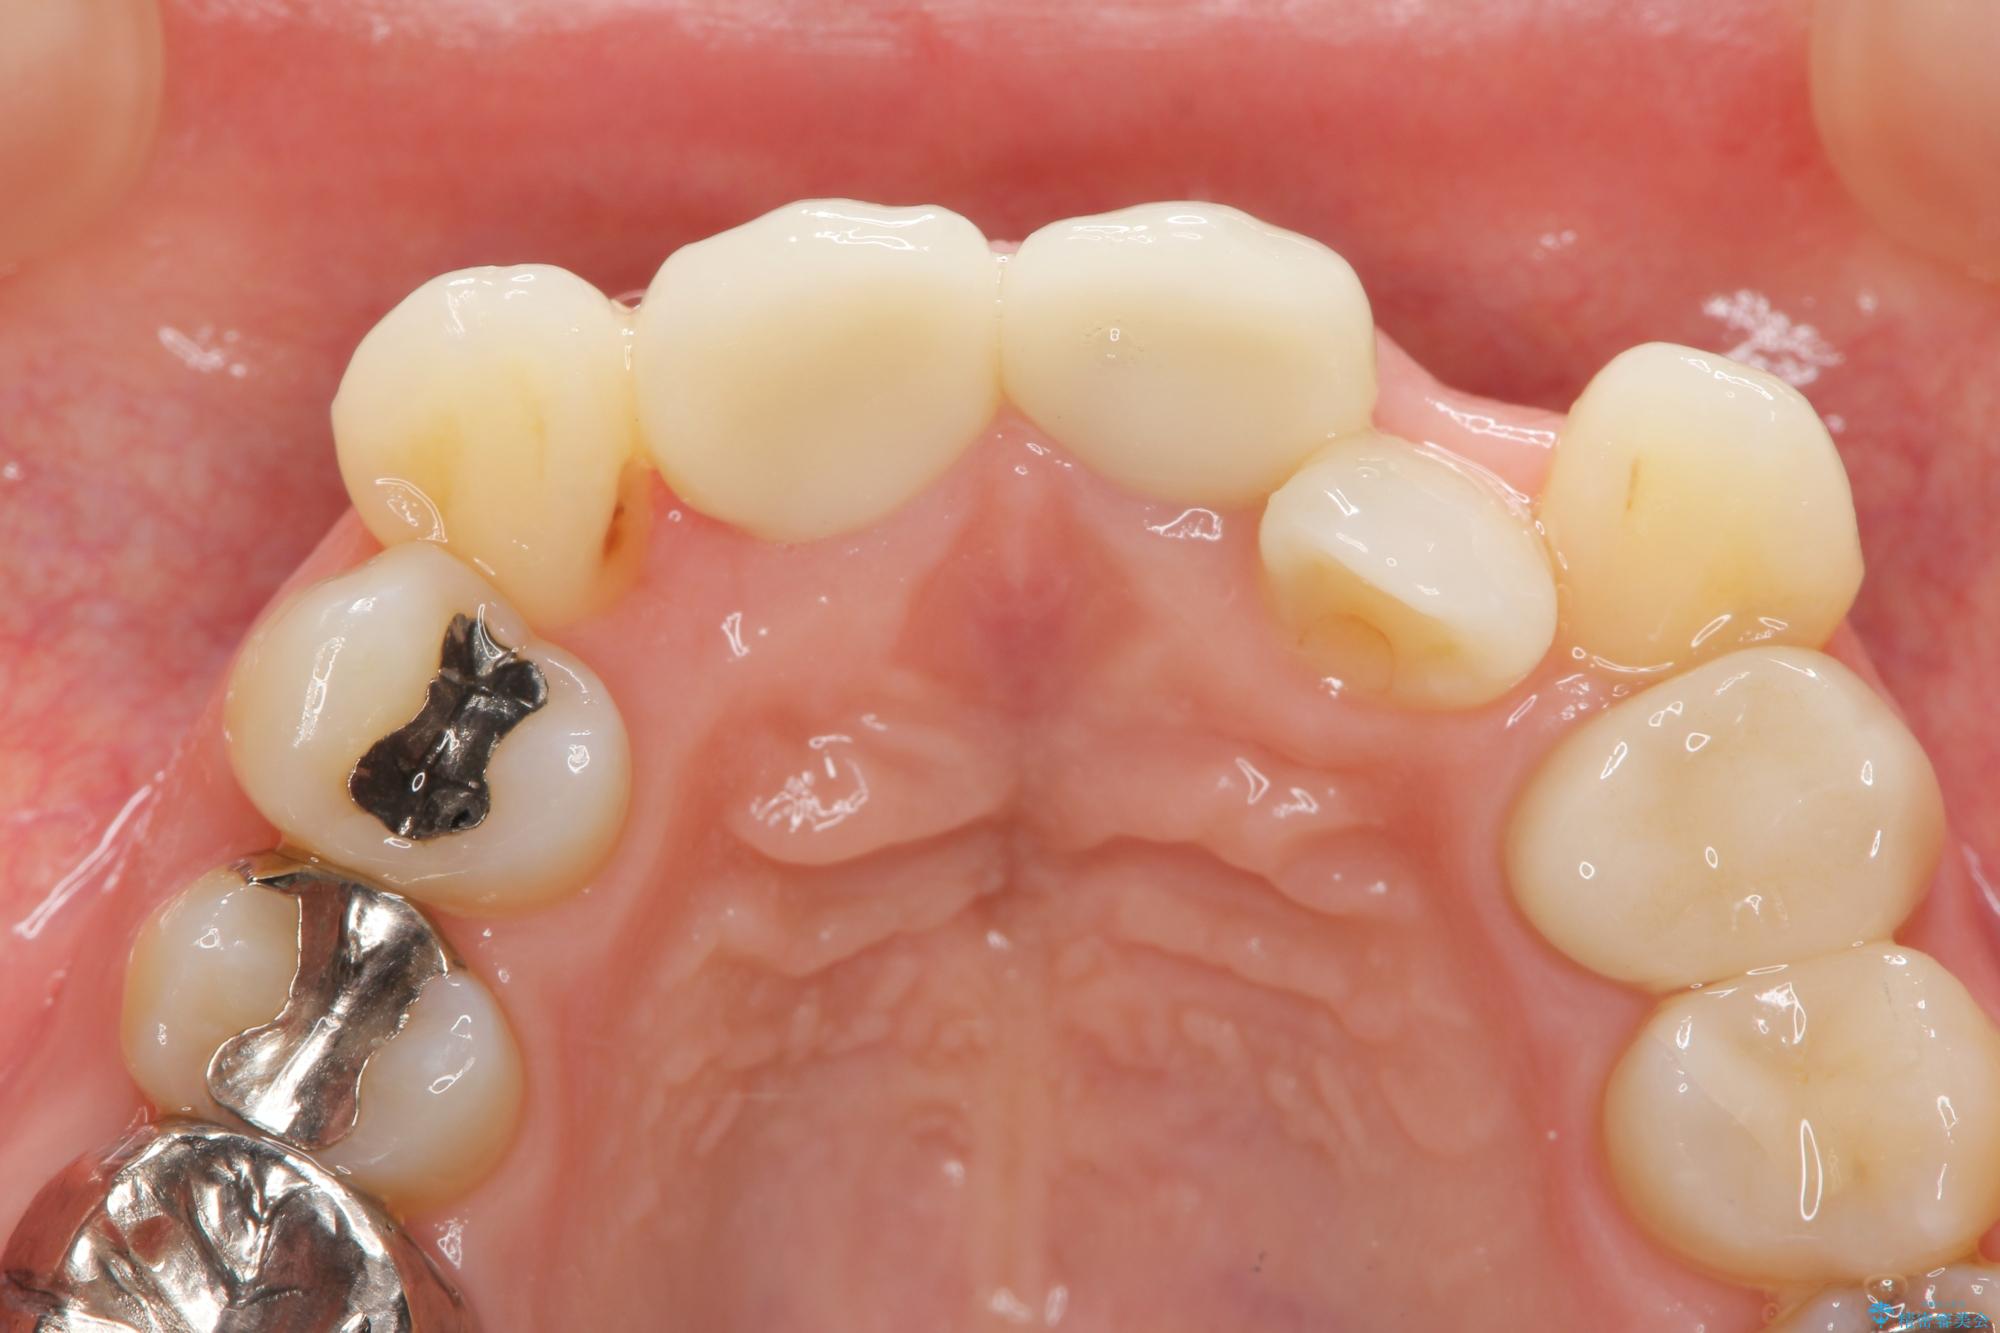

26.4万円(ジルコニアクラウン×2・仮歯×2)

レントゲン検査の結果、以前の根管治療の詰め物が突き出た状態でしたので、まず精密な再治療を行います。同時に、歯磨きがしにくく虫歯の原因になっている右上側切歯を抜歯し、その後、セラミック治療で全体を美しく修復する計画です。

歯磨きがしにくい歯を抜歯することで、今後の虫歯の再発を防ぐ治療計画としました。